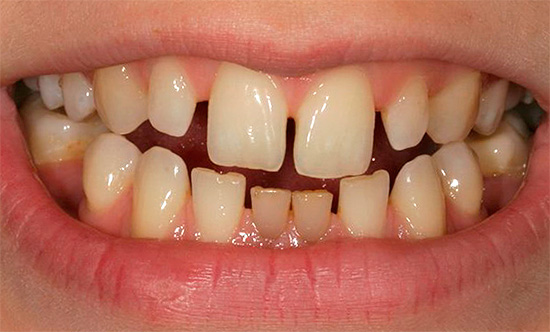

Spesso, con questa anomalia dell'occlusione, è possibile vedere un fenomeno come la compensazione gengivale: i denti sulla mascella superiore sono affollati, mentre sulla grande mascella inferiore si estendono in avanti, sono pari, potrebbero esserci degli spazi tra loro (tre).

Segni facciali del morso mesiale: un profilo convesso, un mento prominente che sporge in avanti, retrazione del labbro superiore e sporgenza del labbro inferiore.